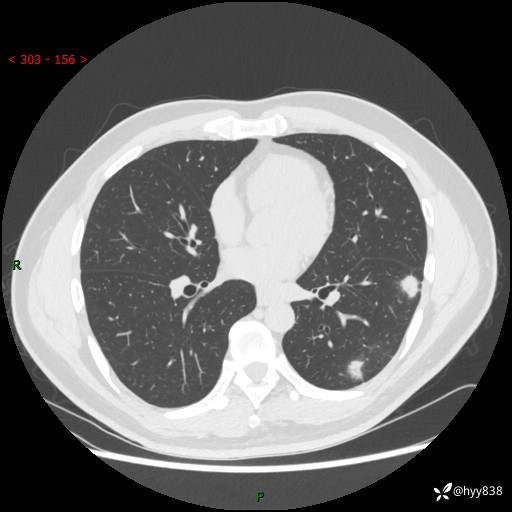

中年男性,胸闷3月余。多发团片、肺小叶分布、空气支气管征、明显强化---结果公布~

现病史:患者3月前出现胸闷,卧位时加重,坐位时缓解,无咽痛、咳嗽,无头痛,无全身酸痛,无结膜充血,无胸痛、心慌,无咯血,无呼吸困难,无咳痰,2024-07-02于当地市第一民医院行胸部CT,结果不详,2024-07-05就诊于我院急诊内科,行胸部CT同时增强,结果示:左肺下叶多发结节灶,考虑感染可能。今患者为求进一步诊治来我院,门诊以“肺部感染”收入我科。 患者本次起病来精神、食欲、睡眠尚可,大小便可,体力,体重无明显变化。

胸部CT平扫+增强

各期CT值:30hu 90hu 77hu